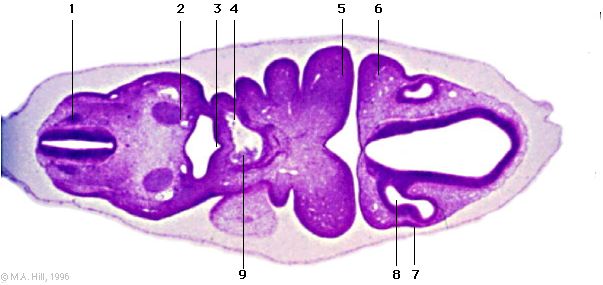

1 |

dorsal root ganglion |

2 |

arch artery 6 |

3 |

laryngotracheal groove |

4 |

arch artery 4 |

5 |

mandibular process |

6 |

maxillary process |

7 |

lens placode |

8 |

optic vesicle |

9 |

aortic sac |